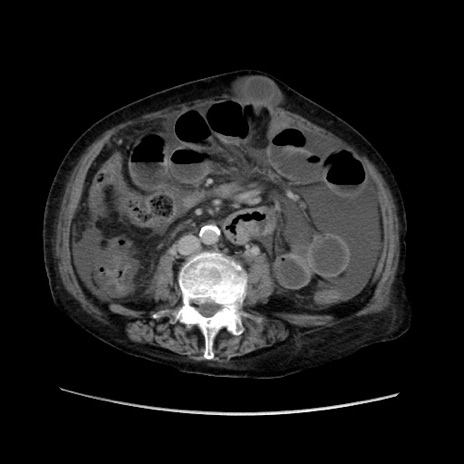

症例31(横断像)

【症例】80歳代 女性

【主訴】腹部膨満感

【現病歴】他院にて肝硬変にてフォロー中。1週間前から便秘、腹部膨満感、臍部腫瘤あり受診となる。

【既往歴】肝硬変

【身体所見】腹部膨隆あり、皮膚変化なし、疼痛なし。

【データ】WBC 4600、CRP 0.25